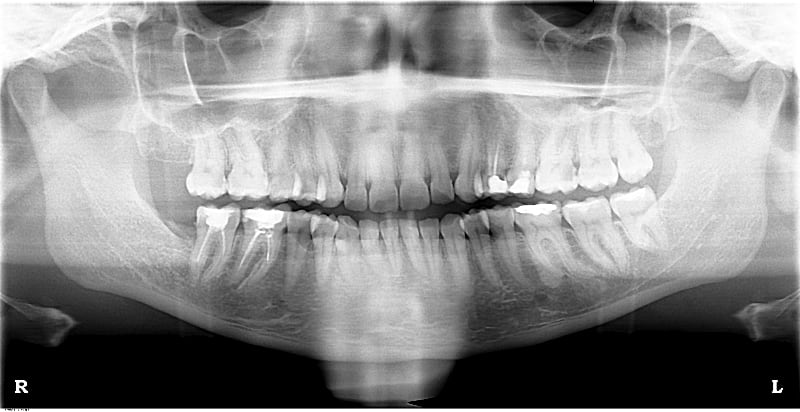

J'ai commencé à réaliser la désobturation d'une 46 où les canaux ont été obturés avec un matériau très dur (gutta ancienne?).

Venue à bout des deux canaux distaux, je peine à arriver à désobturer les parties "terminales" des mv et ml (je n'ai pas voulu forcer au risque de créer une fausse voie).

ca ressembleplus à quelque chose de cassé qu'a de la gutta

la gutta ne resiserait pas au R25

Instruments cassés ! c'est sûr !

Oui c'est ça, je ne suis pas certaine que ce soit de la gutta, c'était un matériau très dur et à la pano assez radio-opaque...

Vous pensez vraiment qu'il y a casse?

Tu as au moins un instrument cassé en mésio lingual et possible en mésio vestibulaire.

Adresse à un endodontiste, sauf si tu arrives à by passer avec limes manuelles...

Peut-être mais dans ce cas précis le canal est calcifié dans la partie apicale.

Tu as fait un très joli travail en distal, en mésial un peu d'essence d'orange disponible à bas prix dans toutes les pharmacies peut être utile s'il s'agit de ciment eugénol et de gutta. Sinon: adresse, ou: referme et fais une couronne.

A noter: caries en distal de 26 et 36, mésial de 17?, 24 et 25 menaçant de s'effondrer nécessitent aussi ton attention.

Tu te paieras de tes bons soins en couronnant 47, 46, 24 et 25.